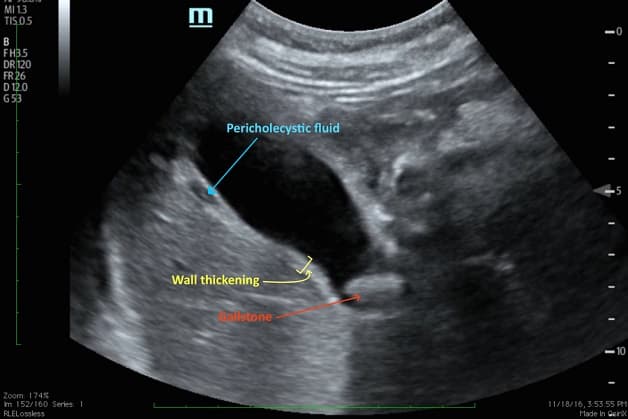

– Siêu âm ổ bụng – để kiểm tra sỏi mật hoặc các vấn đề túi mật khác.

Siêu âm chẩn đoán viêm túi mật cấp tính.